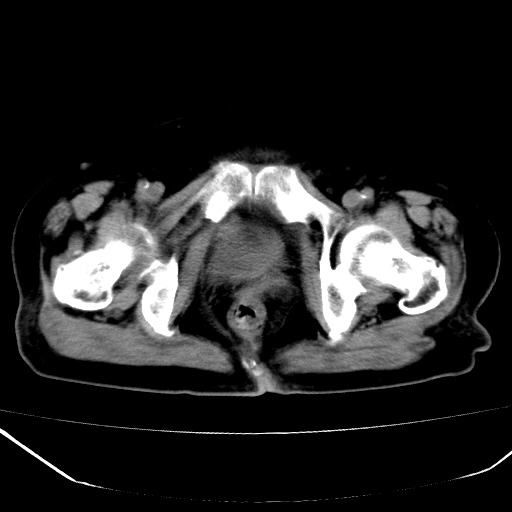

标题: CT18557:盆腔内包块,请指教

患者,女,74岁,无不适,b超示盆腔包块。

子宫前上方巨大脂性肿物,肿物边缘为较厚软组织密度影,其内缘欠光整,脂性密度中央见结节状软组织密度影“漂浮”,肿物与子宫前壁关系密切,考虑1脂肪瘤2皮样囊肿3肌瘤脂样变

ct值-90hu